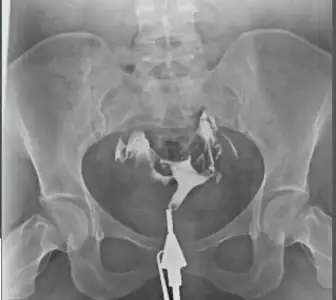

Banada çeken doktor hafif tıkanıklık vardı dedi tazikli ilaç verdim açıldı dedi.sonra klomen kullandım bende tek taraflı 2kist çıktı adet olamadım.çok kötü sancılanıyordum o sıralar 3 4 ayda anca geçti sonra doktorun ilgisini hiç beğenmedim başka doktora gittim oda senin dediğin gibi dedi hiç içine sinmemiş bir taraf açılmamış gibi tekrar yapabilirim dedi bende istemedim.o ay klomen ve çatlatma iğnesi oldum tekrar kist oluştu ondan sonra da bir daha doktora gitmedim.hep aynı şeyler klomen femera . çatlatma iğnesi bıktım artık .ne zaman klomen kullandıysam kist oluştu o yüzden oluruna bıraktım artık.bu ilaçlar bana gelmiyor demekkiCanım ben sana şöyle anlatayım benim 6 ay oldu cektireli haziranda çektirmiştim. O zaman kendi doktorumun olduğu hastanede cihaz bozuktu ne zaman yapılacağı da belli değildi. Doktora sordum başka yerde çektirip size getireyim mi diye o da olur zaman kaybetme ben kabul ederim dedi

Bende başka hastanede cektirdim çeken doktor hiç bi sıkıntı yok dedi

2 ay sonra kendi doktoruma gösterdim bi tüpünden ilaç yavaş geçmiş çeken doktor ne dedi dedi

Bende sorun yokmuş dedim benimde görmem lazım böyle emin olamıyorum dedi

Yani önce kabul ederim demişti şimdi benimde görmem lazım diyor 4 aydır ayni şeyi söylüyor hatta en son aşılama olmazsa isterim ama film dedi şimdi Bende napicam bilmiyorum ben o kağıdı ekliyorum şimdi

Ben 2 kere klomen 2 kere letu kullandım bende hiç kist olmadı ama zaten benim cikolata kistim var sağda. Hafif yavaş geçmiş dedigi de sol taraf. Kağıtta da açıldığına benzer bi yazı yazıyor zaten demekki doktor açmış yavaş geçse bile. Ki ben üstüne basa basa çeken doktora sordum tüpler de falan bisey var mı diye çünkü ilk kagidi aldım doktorda hayır hiç bisey yok tertemiz dedi. Görüntü var şimdi ekliyorumBanada çeken doktor hafif tıkanıklık vardı dedi tazikli ilaç verdim açıldı dedi.sonra klomen kullandım bende tek taraflı 2kist çıktı adet olamadım.çok kötü sancılanıyordum o sıralar 3 4 ayda anca geçti sonra doktorun ilgisini hiç beğenmedim başka doktora gittim oda senin dediğin gibi dedi hiç içine sinmemiş bir taraf açılmamış gibi tekrar yapabilirim dedi bende istemedim.o ay klomen ve çatlatma iğnesi oldum tekrar kist oluştu ondan sonra da bir daha doktora gitmedim.hep aynı şeyler klomen femera . çatlatma iğnesi bıktım artık .ne zaman klomen kullandıysam kist oluştu o yüzden oluruna bıraktım artık.bu ilaçlar bana gelmiyor demekki